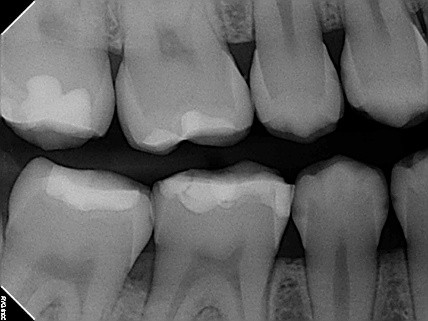

2 / 50

2. (Select ONE OR MORE correct answers)

The radiograph shows evidence of